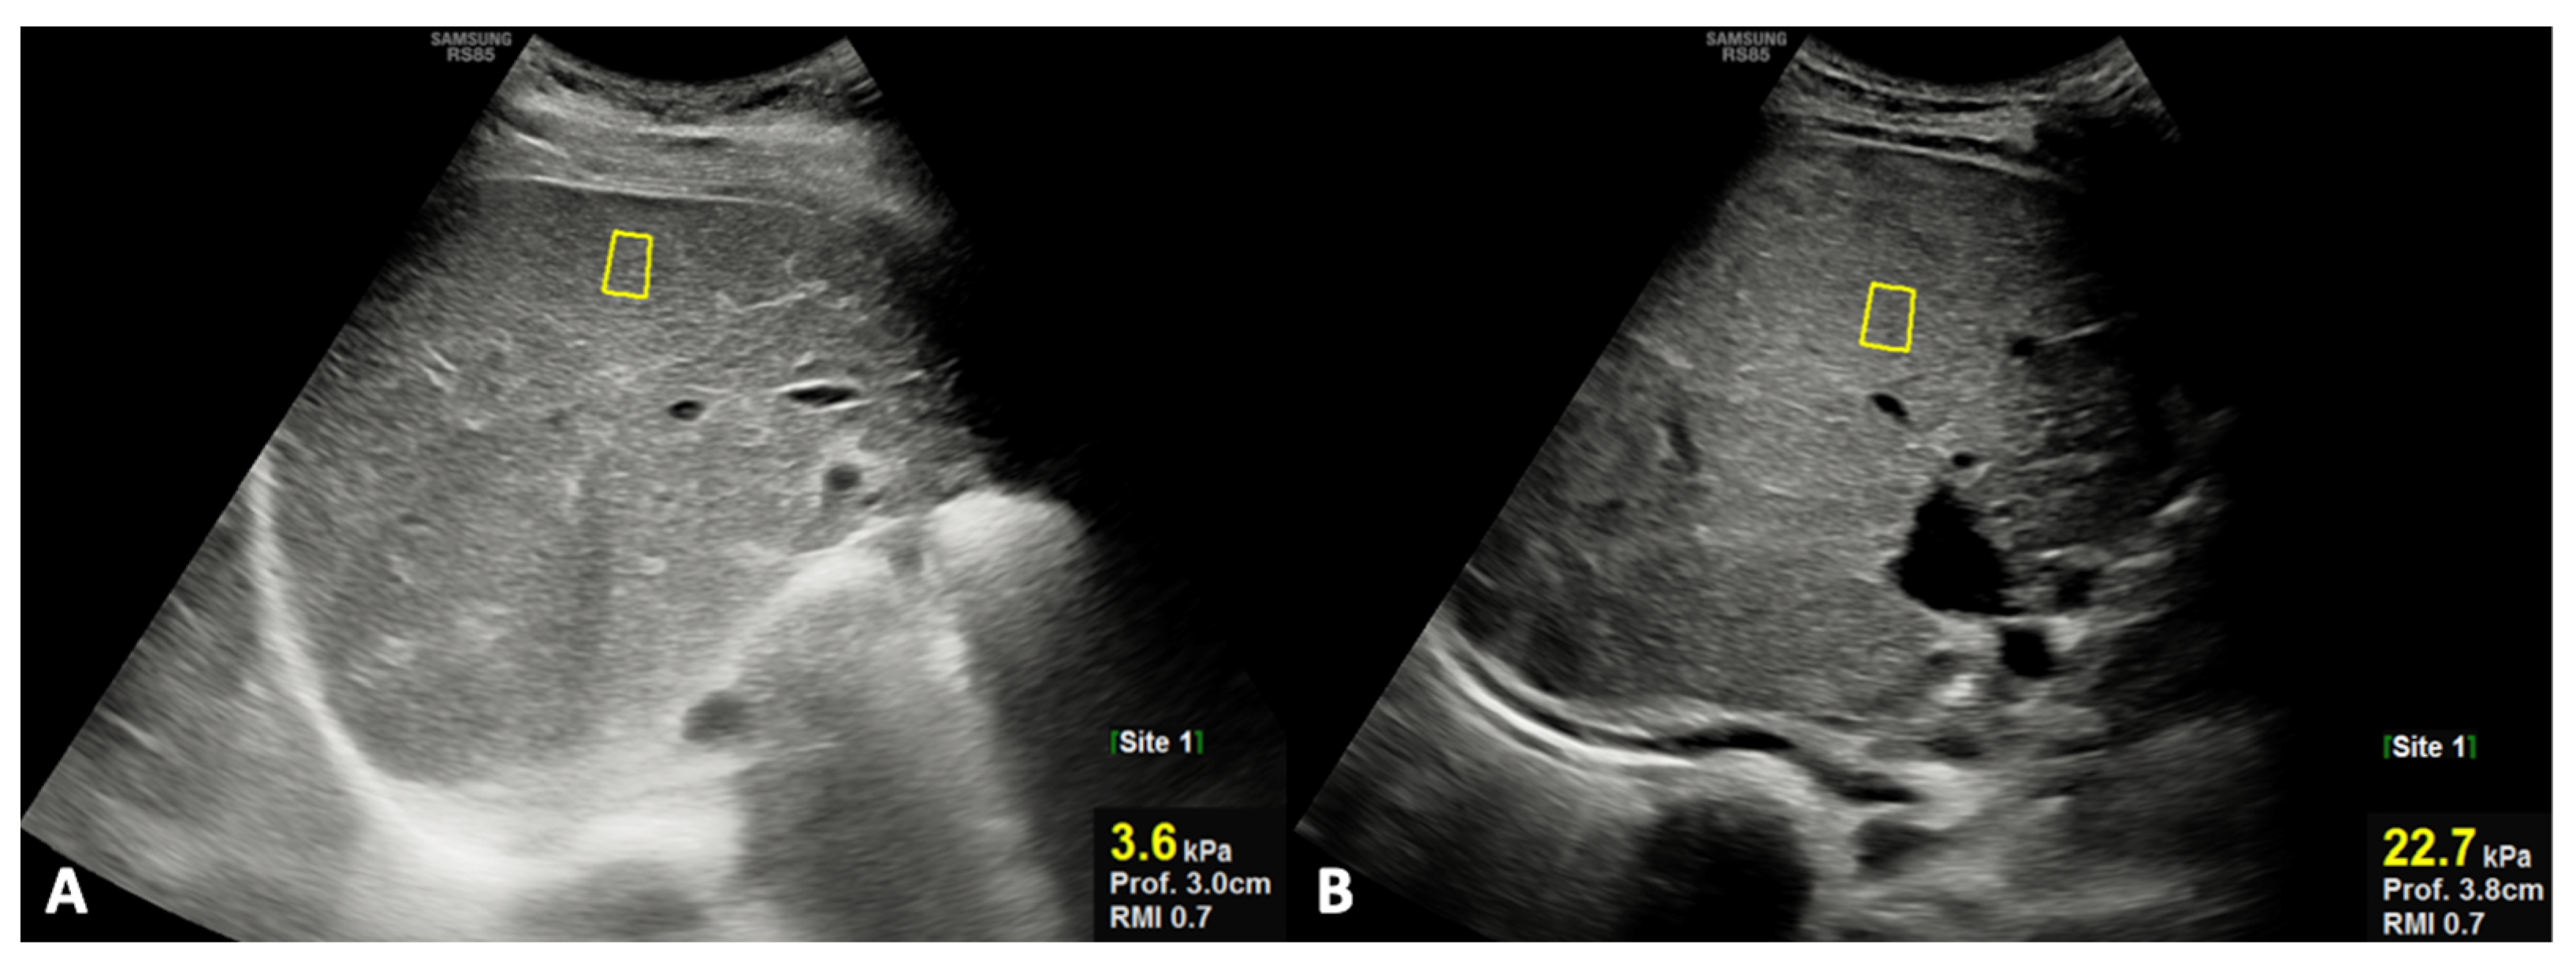

| Liver stiffness (kPa) | 5.95 ± 1.28 | 10.47 ± 7.32 | 0.020 | |